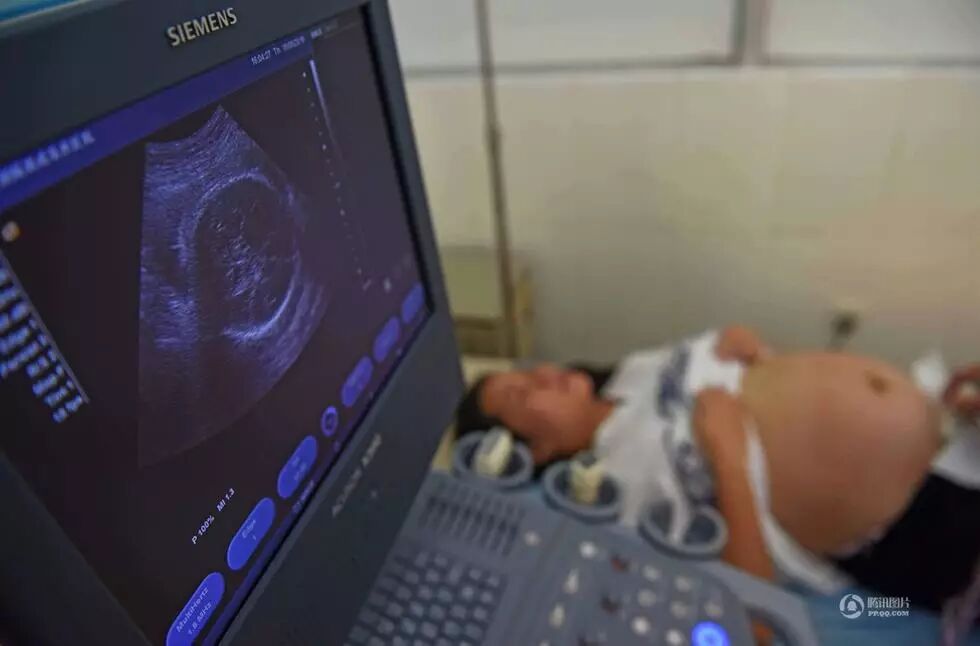

怀孕后,杨奕青回到艾滋病专管区医院上班,不管天气多热,她都穿上一件加厚的白大褂。在她工作的区域内,艾滋病戒毒人员随处可见。